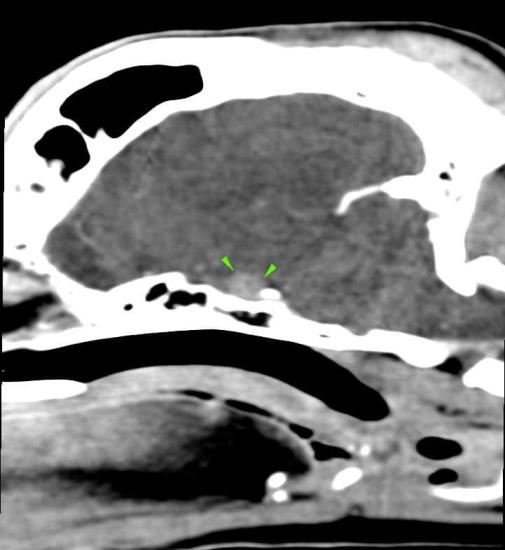

A 8-year-old cocker spaniel was referred for polyuria/polydipsia and polyphagia. The abdominal ultrasound revealed bilateral symmetric adrenal enlargement (images below). A CT scan of the head was performed. A round, 7mm, contrast-enhancing nodule was found at the level of the pavement of the sella turcica, in the hypophyseal fossa (green arrowheads).

A final diagnosis of pituitary-dependent hyperadrenocorticism was made.